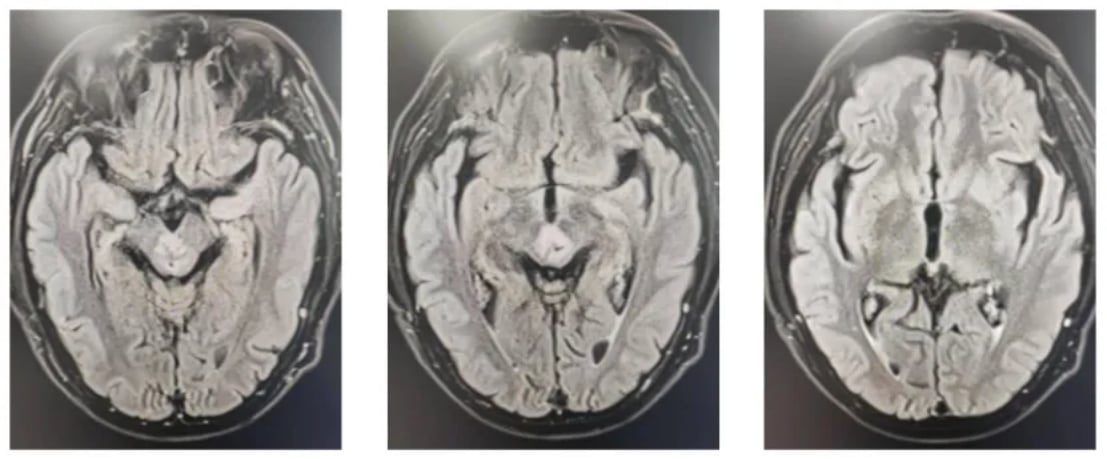

确诊后,患者于2023年6月开始了首次治疗,采用了脑局部适形调强放疗(IMRT)联合同期化疗的方案。化疗药物选择了替尼泊苷(Teniposide)。在为期一个多月的同步放化疗期间,患者耐受性良好,未出现明显的血液毒性反应,且左眼睑下垂的症状有所改善。治疗结束后的影像学复查显示,脑内多处病灶较治疗前明显缩小,治疗效果显著。

图2 首次治疗后复查影像学

随后,患者继续接受了12个疗程的替尼泊苷单药辅助化疗,病情持续稳定。